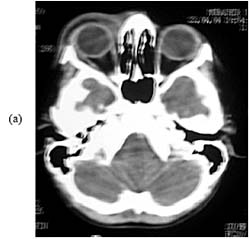

Một bệnh nhi nam 9 tuổi nhập viện vào phòng cấp cứu với biểu hiện sốt, nôn mửa liên tục, nhức đầu dữ dội trong 2 ngày qua. Sốt thường từng cơn có thể lên đến 101oF. Nhức đầu liên tục , chủ yếu nhức đầu vùng trán và thái dương và ho rất nghiêm trọng. Bệnh nhi bị sưng mắt phải lan tỏa chủ yếu vùng mi mắt với dấu hiệu chảy nước mắt và sợ ánh sáng nhưng không đỏ mắt. Bệnh nhân có tiền sử sốt viêm ruột cách đây 2 tháng và được cho dùng kháng sinh điều trị trong 2 tuần. Trước đó bệnh nhi hoàn toàn khỏe mạnh, không đi du lịch ra khỏi Pakistan hoặc ăn phải một loại hải sản nào khác. Nhà có nuôi 5 con mèo và trẻ này thình thoảng hay chơi đùa với chúng. Khám tổng quá chung bệnh nhi cho thấy trẻ lo âu và dễ bị kích thích với sưng mắt rõ ràng. Thân nhiệt lúc này 102oF, mạch 90/phút, nhịp thở 21/phút và huyết áp 110/70 mmHg. Khám mắt cho thấy sưng mi mắt trên bên (P), đỏ nhẹ và cử động mắt có phần giới hạn, đặc biệt nhìn chằm chằm phía trên. Soi đáy mắt kết quả bình thường. Khám chuyên khoa thần kinh cho thấy dấu cứng cổ nhưng không có dấu hiệu thần kinh cục bộ. Khám các cơ quan khác còn lại bình thường. Các xét nghiệm cận lâm sàng lúc nhập viện cho thấy: bạch cầu chung 33.400/øL với tỷ lệ bạch cầu đa nhân trung tính 13%, lymphocyte 8%, monocytes 2%, eosinophils 77%; tiểu cầu 318.000/øL; tốc độ máu lắng 24 mm/giờ. Dịch não tủy (CSF) cho biết số lượng bạch cầu chung 360/øL với 10% đa nhân trung tính và 90% eosin, glucose 83 mg/dl, protein 14 mg/dl. Nhuộm dịch não tủy cho kết quả âm tính. Cấy máu và dịch não tủy vô trùng với các tác nhân gây bệnh. Chụp cắt lớp (CT) não cho thấy có tăng màng não, phù não và sưng phồng quanh ổ mắt bên (P) (Hình 1).

Hình 1: Kết quả CT scan cho thấy mô mềm sưng phồng vị trí phía bên phải (a). không có tổn thương dạng khối nhưng có phù não và tăng âm vùng màng não-tủy mềm (leptomeninges) trên phim chụp cản quang sau cho thấy hình ảnh viêm màng não-tủy mềm (leptomeningitis). Các kết quả khác như xét nghiệm máu ngoại vi cho thấy tăng bạch cầu eosin với hình thể bình thường, xét nghiệm phân, kể cả phương pháp tập trung trứng và ký sinh trùng đều âm tính trên 4 mẫu phân. Toxoplasma IgM (-) và nồng độ IgE trong huyết thanh toàn phần trong giới hạn bình thường. Chọc hút tủy xương cho thấy tăng bạch cầu giai đoạn tiền eosin tăng nhưng hình thể bạch cầu bình thường.